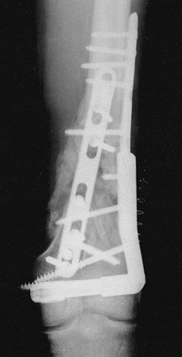

stabilizing comminuted proximal and distal periarticular fractures,

which often provide only short metaphyseal or epiphyseal fragments for

pin insertion. With simple frame modifications (Fig. 11.21B; Fig. 11.23, items 3 and 4),

however, these fractures are easily managed. Proximally, where the safe

corridor opens wide, subchondral pin placement affords anchorage for

two or more half or full pins (Fig. 11.21B, Fig. 11.21C and Fig. 11.24D). Over two or more longitudinal

rods, these pins are then rigidly connected to several distal pins,

which in the tibia are placed close to the sagittal plane. After the

application of these frames, the knee is moved through a full range of

motion to ensure free mobility of joint capsule, pes anserinus, and

iliotibial band. Distal tibial fragments as short as 2 or 3 cm long can

be stabilized by inserting two or more pins on either side of a

longitudinal rod (Fig. 11.23, item 4).